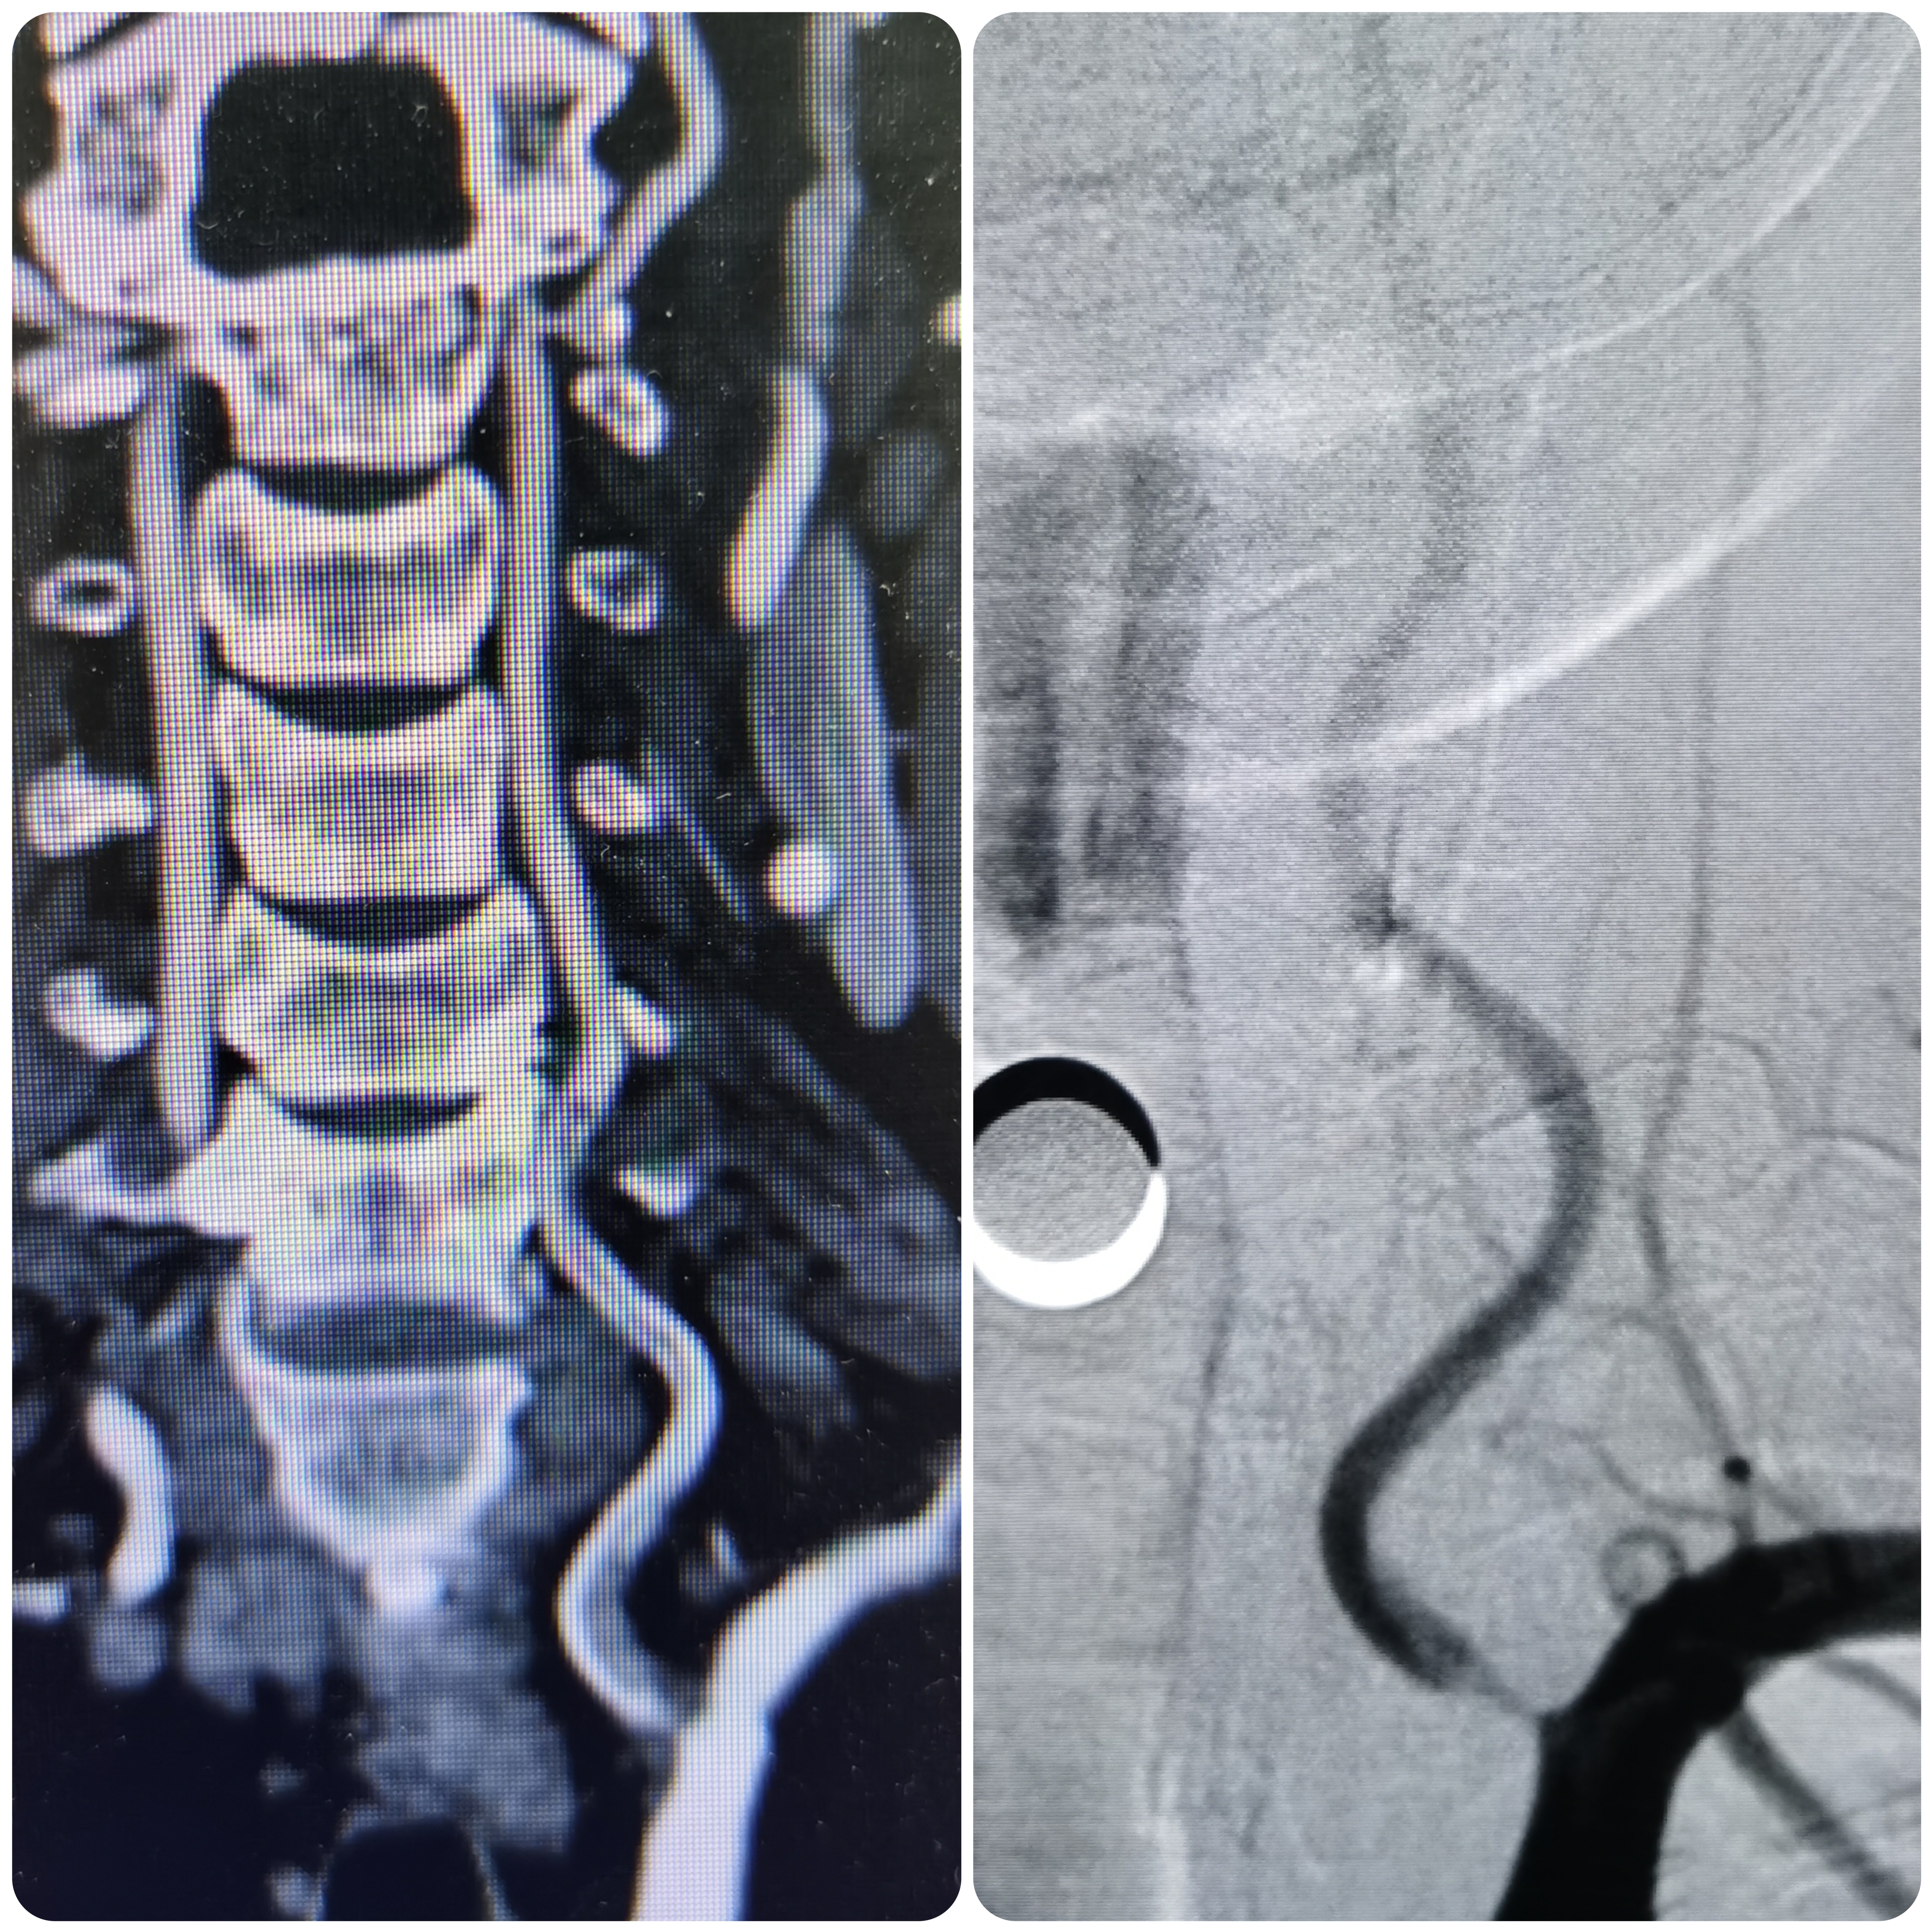

患者PXY,男性,55岁,因突发头晕、恶心、呕吐2.5小时来院。患者于2.5小时前开车过程中自觉头晕,呈昏沉感,恶心呕吐多次,变换体位时加重,无肢体无力,遂急诊来院。

1、本例患者临床表现为头晕,恶心,呕吐后循环缺血症状,急诊CT除外出血后给予静脉溶栓治疗。经内科治疗后症状逐渐改善。但患者无卒中高危因素,需完善脑血管相关检查。

2、CTA证实左椎动脉起始部重度狭窄合并血栓,系责任血管,存在急性闭塞或残存血栓脱落至基底动脉风险,需积极处理。